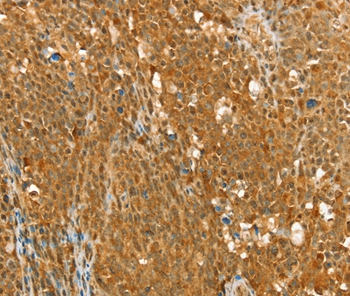

Immunohistochemical analysis of paraffin-embedded Human ovarain cancer tissue using #36712 at dilution 1/25.